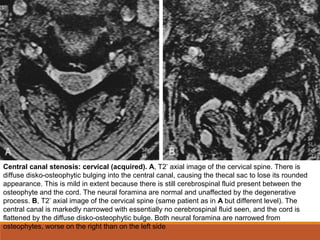

Central canal stenosis: cervical (acquired). A, T2*

axial image of the cervical spine. There is

diffuse disko-osteophytic bulging into the central canal, causing the thecal sac to lose its rounded

appearance. This is mild in extent because there is still cerebrospinal fluid present between the

osteophyte and the cord. The neural foramina are normal and unaffected by the degenerative

process. B, T2*

axial image of the cervical spine (same patient as in A but different level). The

central canal is markedly narrowed with essentially no cerebrospinal fluid seen, and the cord is

flattened by the diffuse disko-osteophytic bulge. Both neural foramina are narrowed from

osteophytes, worse on the right than on the left side

Central canal stenosis:cervical (acquired). A, T2* axial image of the cervical spine. There is diffuse disko-osteophytic bulging into the central canal, causing the thecal sac to lose its rounded appearance. This is mild in extent because there is still cerebrospinal fluid present between the osteophyte and the cord. The neural foramina are normal and unaffected by the degenerative process. B, T2* axial image of the cervical spine (same patient as in A but different level). The central canal is markedly narrowed with essentially no cerebrospinal fluid seen, and the cord is flattened by the diffuse disko-osteophytic bulge. Both neural foramina are narrowed from osteophytes, worse on the right than on the left side